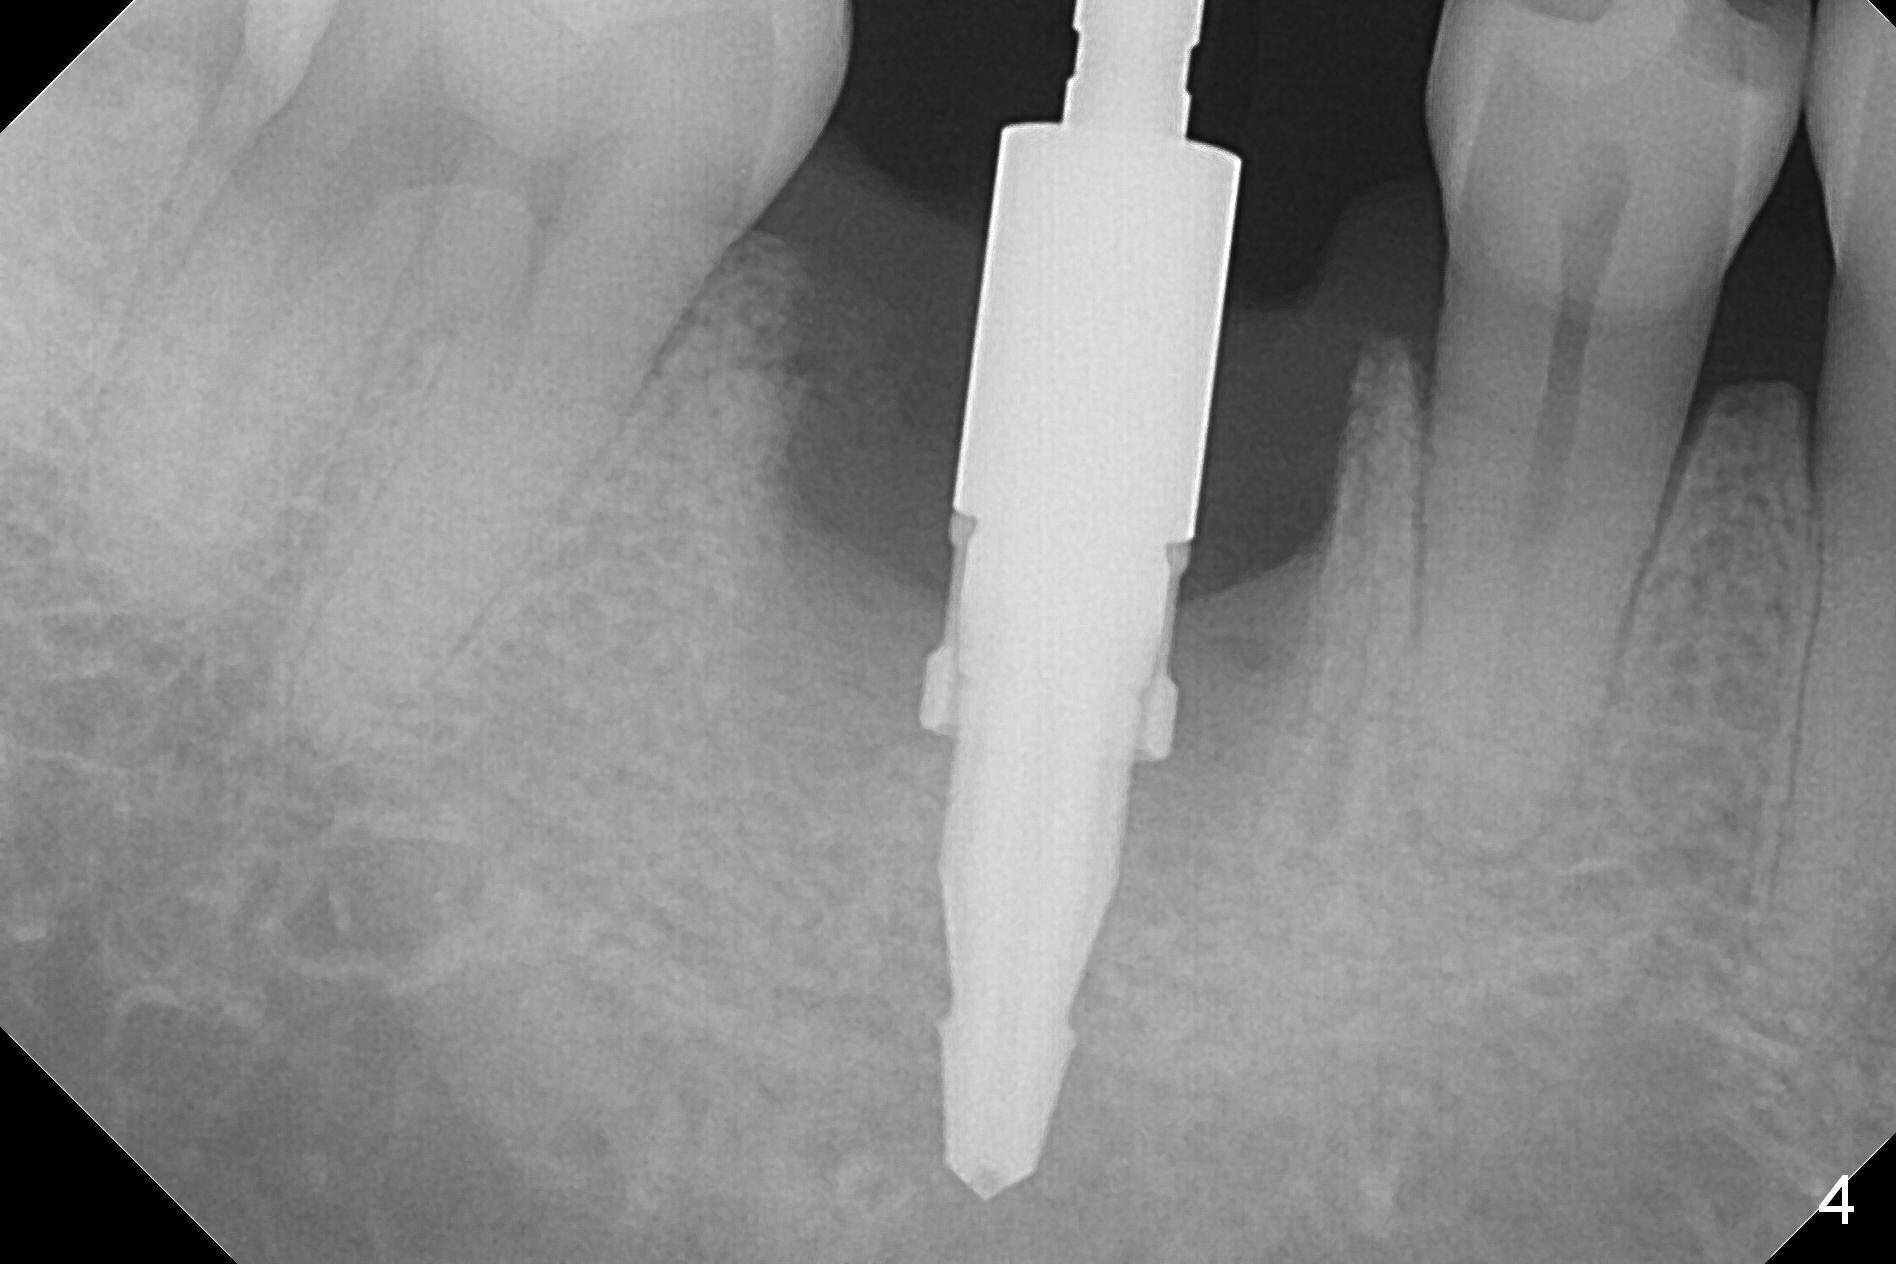

After extraction of the tooth #30 with Class V furcation involvement (Fig.1 (>),2 (L: lingual)), initial osteotomy depth is 8 mm with infiltration anesthesia, but a parallel pin is able to be inserted for 16 mm without pain (Fig.3). There is oozing from the osteotomy. Osteotomy increases in diameter with depth at 8 mm (Fig.4 (3.8 mm drill),5 (5.3 mm tap)). As the Inferior Alveolar Canal (IAC) is indistinct with increased pain during osteotomy, a 5.9x6 mm implant is placed with >50 Ncm following Septocaine infiltration (Fig.6). When bone graft (Fig.7 *) and 7.8x5.5(6) mm abutment (Fig.7,8) are placed, panoramic X-ray is taken (Fig.9). There appears to be a thick layer of spongy bone in the posterior mandible between the red and yellow dashed lines (Fig.5,9). Panoramic X-ray and/or CBCT should be taken if preop PA does not reveal IAC. This patient seems to be a bruxer. There are mandibular tori. Bone loss (furcation involvement) is not proportional to his oral hygiene status. Functional loading (progressive) should be delayed due to bruxism and the short implant.